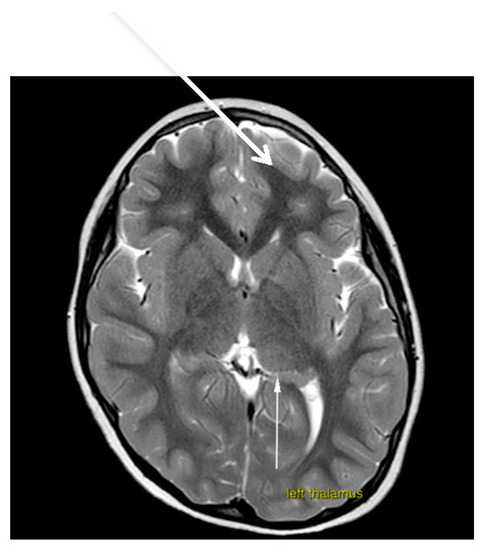

Brain magnetic resonance imaging (MRI) demonstrated hypoplasia of the brainstem (Figure 2), a left thalamus volume larger than the right (Figure 3), an enlarged fourth ventricle, an anterior and posterior midline bulbar and pontine cleft (split-pons sign) (Figure 4), a butterfly configuration of the medulla (Figure 5), an occipital and parietal plagiocephaly on the right side, and a slight benign enlargement of the subarachnoid spaces in the frontotemporal area. There were no signal changes within the medulla or pons in any of the brain MRI sequences.

Figure 4. MRI brain axial T2-weighted image showing split pons sign.